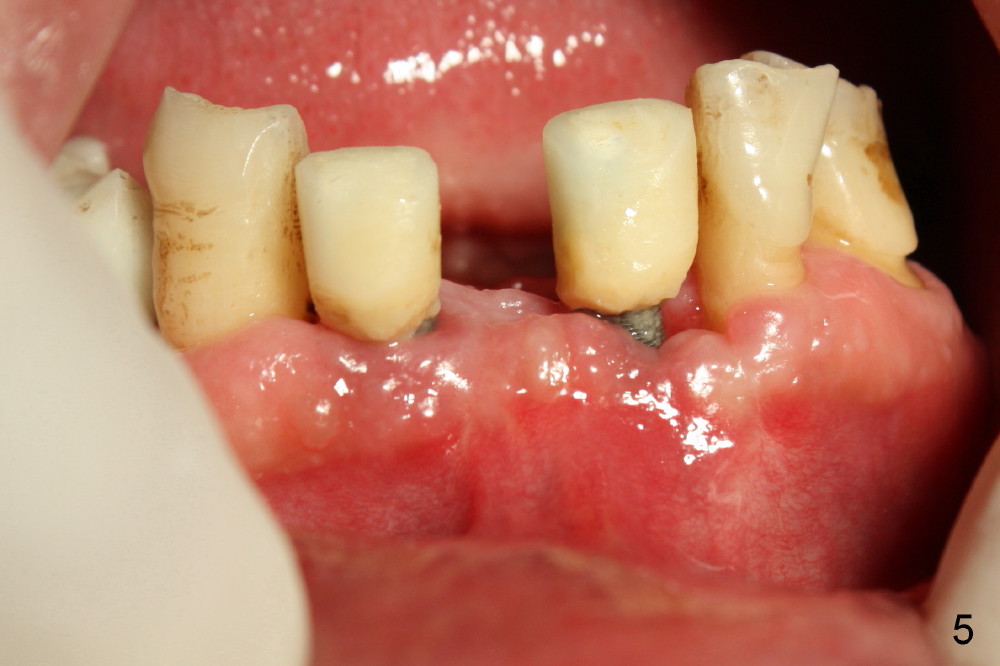

The mesial incision is found to dehiscence 7 days postop (Fig.3). Perio dressing dislodges one day postop. Perio dress is re-applied at follow up, but it is detached soon. Fortunately the wound shows sign of healing 14 days postop (Fig.4). The wound heals 5 weeks postop, although the top microthreads are exposed (Fig.5). In all, incision should be avoided as much as for immediate implants, anterior and posterior.